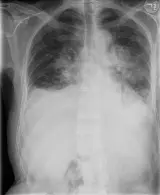

Over 2,100 interactive radiology cases, curated by radiologists for your level of training. Scroll, window, and view cases full screen — just like on PACS. Click linked findings in each writeup to jump straight to them on the image. Cases include sample reports, a focused discussion section, original illustrations, and videos.

PACSで期待されるツールを完備した完全インタラクティブな症例 — スクロール、ウィンドウ調整、ズーム、パン、計測、ROI、フルスクリーンモード。

重要な所見を症例画像上に直接ハイライトする豊富なアノテーション。症例解説内のリンクされた所見をクリックすると、スキャン上の正確な位置へジャンプできます。

職場のPACSステーションと同じようにスクロール、パン、ウィンドウ調整、ズームが可能